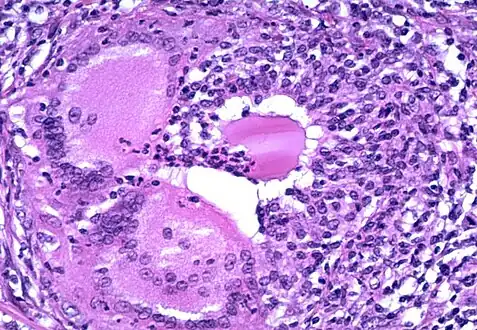

a) Grade 1 thyroiditis characterized by presence of increased number of lymphocytes b) Grade 2 thyroiditis shows the presence of Hurthle cells, epithelioid cells, giant cells, and anisonucleosis c) Grade 2 thyroiditis shows the presence of Hurthle cells with lymphocytic infiltration d) Grade 3 thyroiditis characterized by presence of florid lymphocytic infiltration

Microscopic image showing inflammation of the thyroid tissue